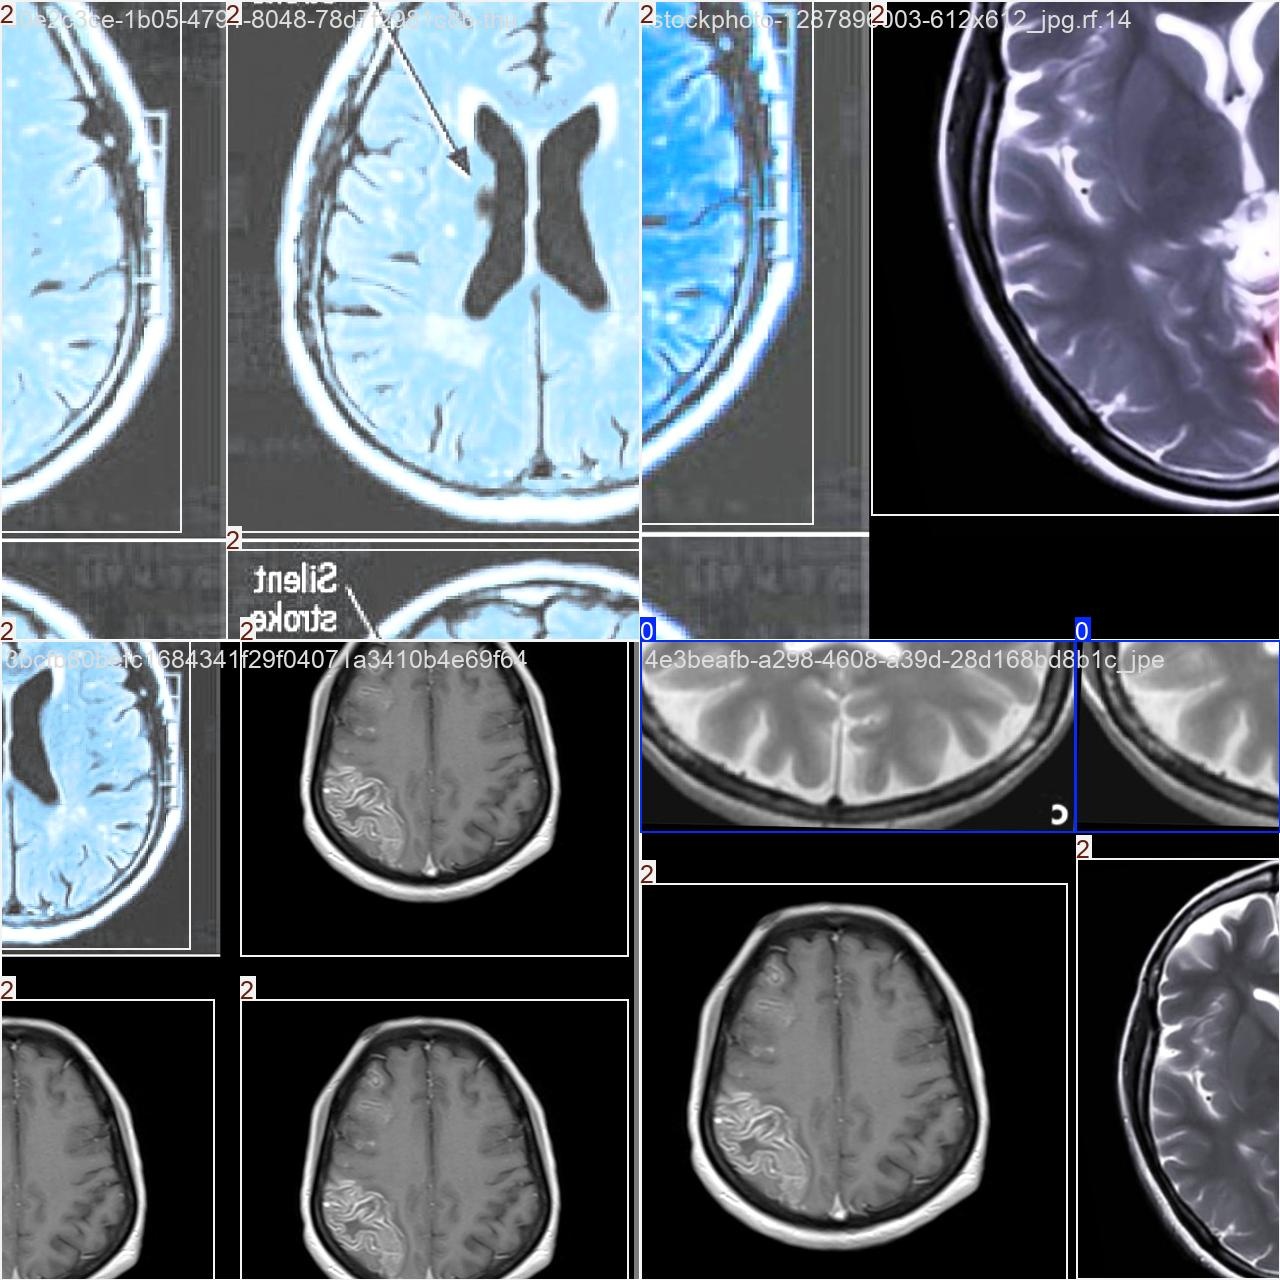

基于YOLO格式的脑部疾病(癫痫、脑中风)目标检测数据集

图片总数:共计2646张图片。其中训练集包含1852张图像、验证集有529张图像、测试集则包含265张图像。标注文件格式:YOLO标记文件无需额外处理即可直接导入模型进行训练

Category: Epileptic brain disorders, Category: Strokes are a form of brain disorders, Category: The functional integrity of the brain is normal

目标检测训练数据可视化

在目标检测训练过程中,在数据可视化方面的结果显示了各分类目标的边界框及其对应标签。整体检测效果较为理想。然而,在当前阶段的基础上通过改进标注质量和强化模型训练能够进一步提高精确度与鲁棒性。